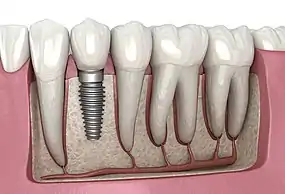

A dental implant (also known as an endosseous implant or fixture) is a prosthesis that interfaces with the bone of the jaw or skull to support a dental prosthesis such as a crown, bridge, denture, or facial prosthesis or to act as an orthodontic anchor. The basis for modern dental implants is a biological process called osseointegration, in which materials such as titanium or zirconia form an intimate bond to the bone. The implant fixture is first placed so that it is likely to osseointegrate, then a dental prosthetic is added. A variable amount of healing time is required for osseointegration before either the dental prosthetic (a tooth, bridge, or denture) is attached to the implant or an abutment is placed which will hold a dental prosthetic/crown.

Single tooth implant restoration

Single tooth restorations are individual freestanding units not connected to other teeth or implants, used to replace missing individual teeth.[11] For individual tooth replacement, an implant abutment is first secured to the implant with an abutment screw. A crown (the dental prosthesis) is then connected to the abutment with dental cement, a small screw, or fused with the abutment as one piece during fabrication.[15]: 211–232 Dental implants, in the same way, can also be used to retain a multiple tooth dental prosthesis either in the form of a fixed bridge or removable dentures.